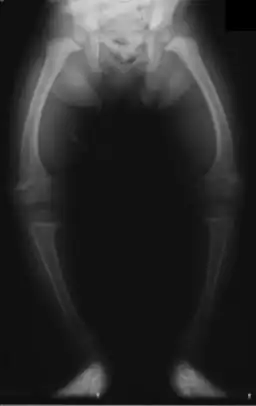

The X-ray, or radiograph, in the article is the classic image of advanced rickets sufferers: bow legs (outward curve of long bone of the legs) and a deformed chest. Changes in the skull also occur causing a distinctive "square headed" appearance. These deformities persist into adult life.